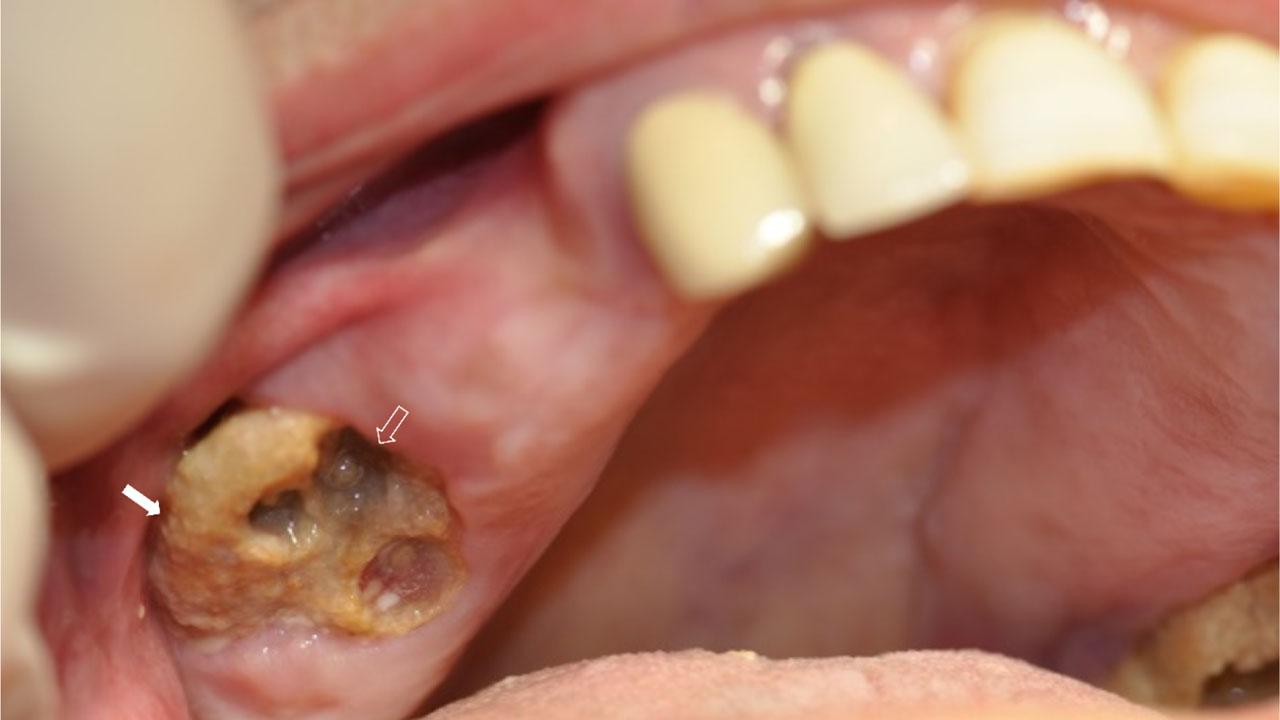

Figure 1:

Osteonecrosis of the maxilla, presenting as exposed necrotic bone (compact arrow), after a dental extraction. Sockets without teeth (phantom sockets) (transparent arrow), are seen on the necrotic bone. Patient was asymptomatic at presentation.